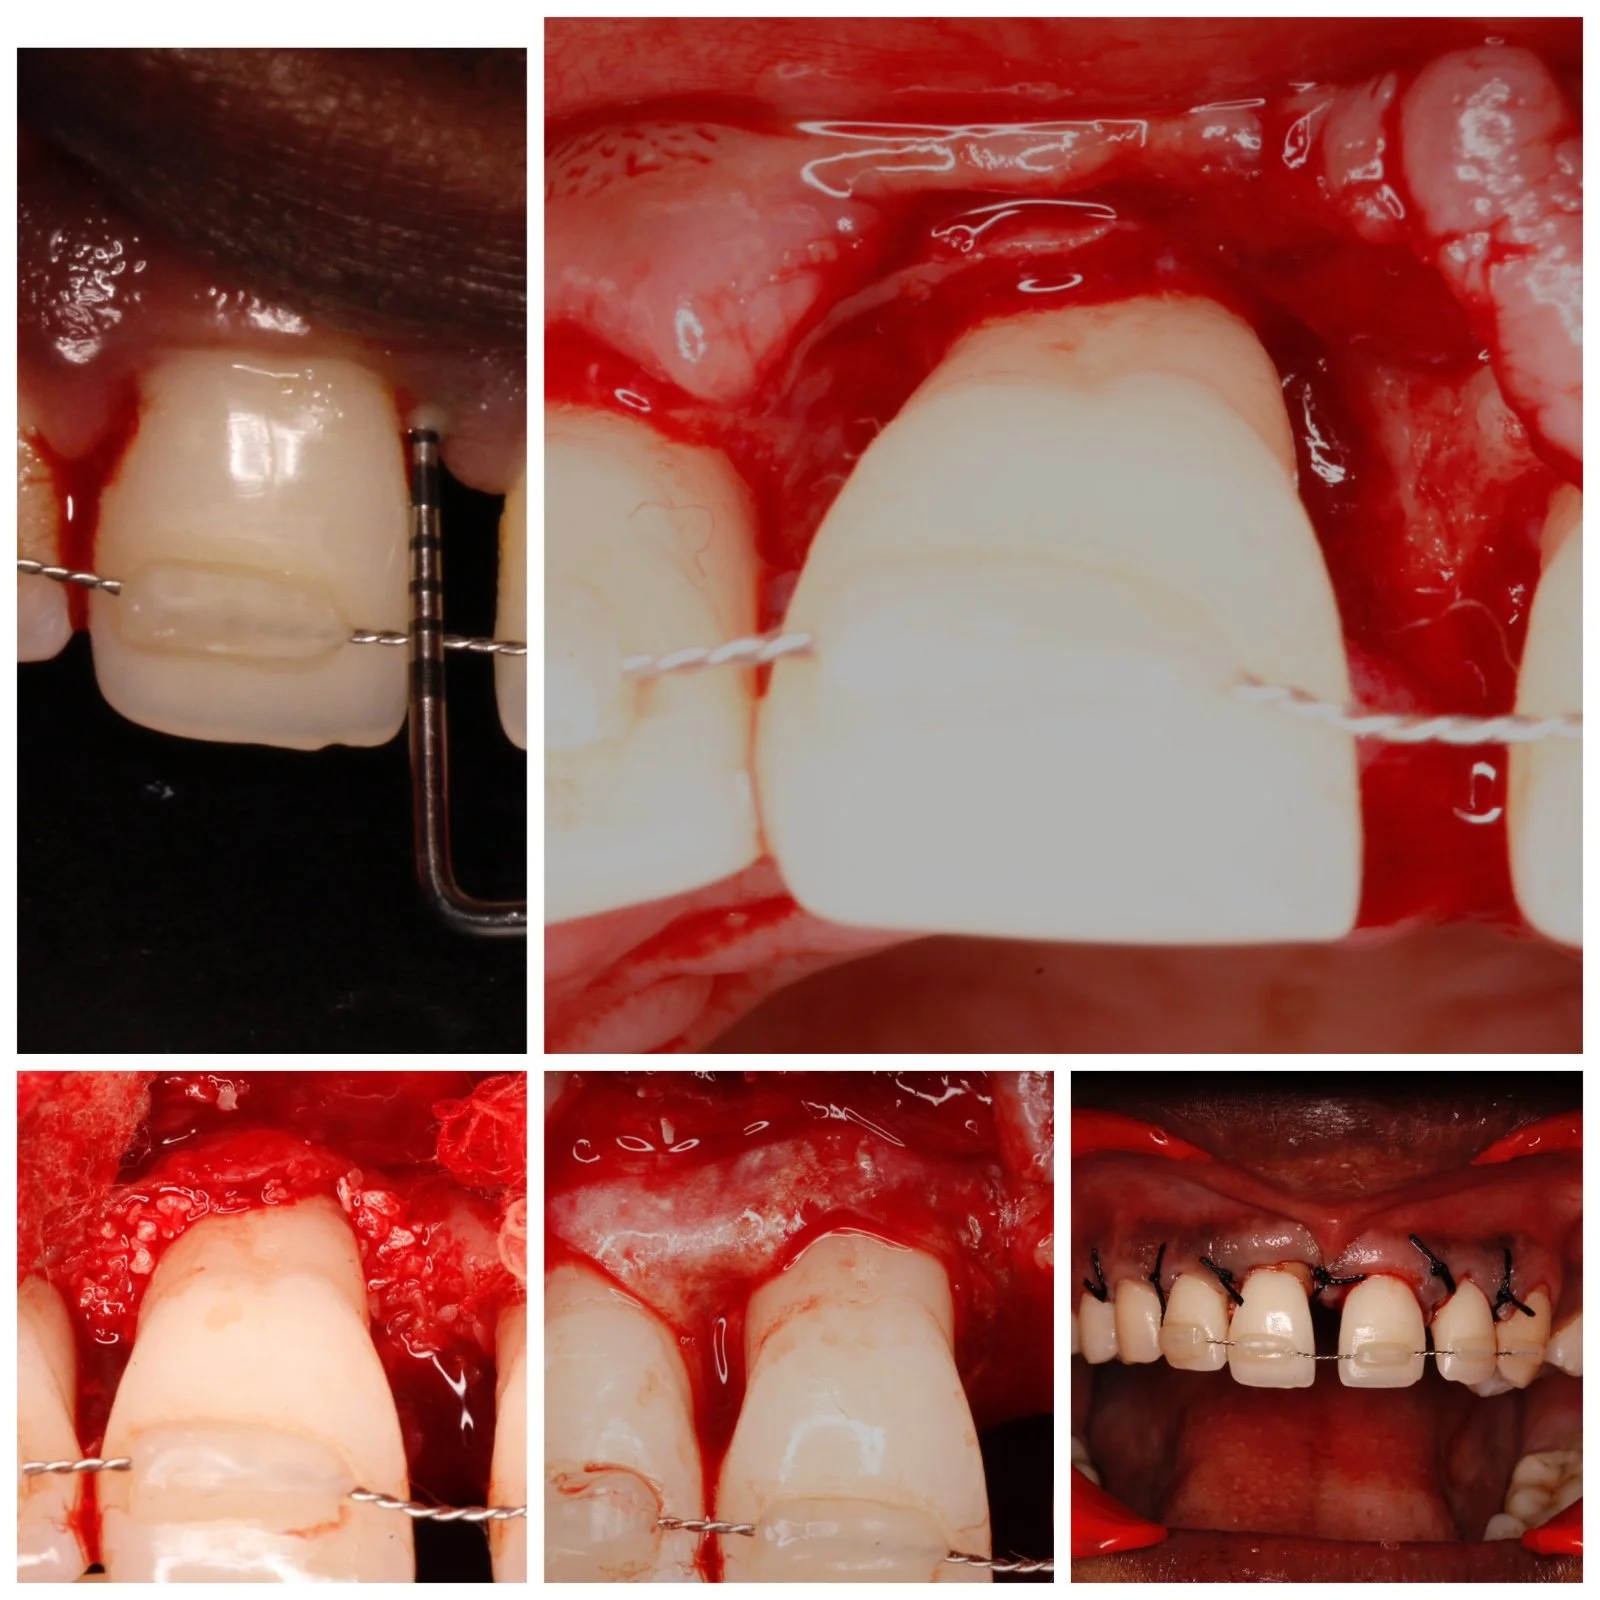

Ridge augmentation in relation to upper anterior teeth

Case done by Dr Nivedha